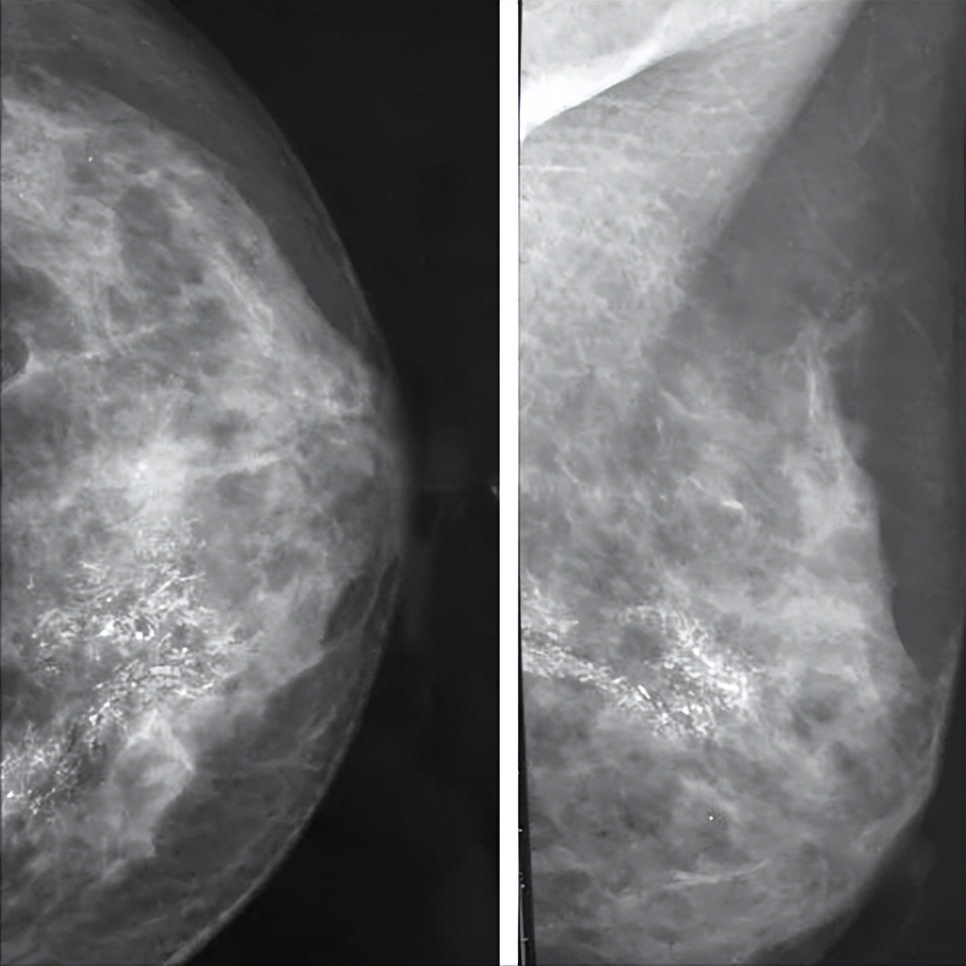

左边恶性结节,右边良性结节

乳腺癌钼靶钙化灶